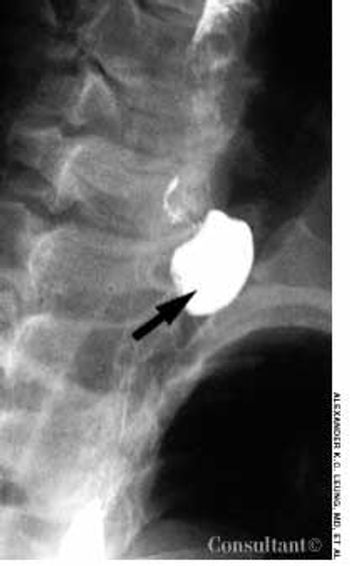

This 8-month-old girl presented with chronic constipation, which had begun during the neonatal period. She had her first bowel movement at 72 hours of age. Since then, she has had bowel movements once every 3 to 4 days. Her stools are pelletlike. Results of thyroid function tests done when she was a neonate were normal.